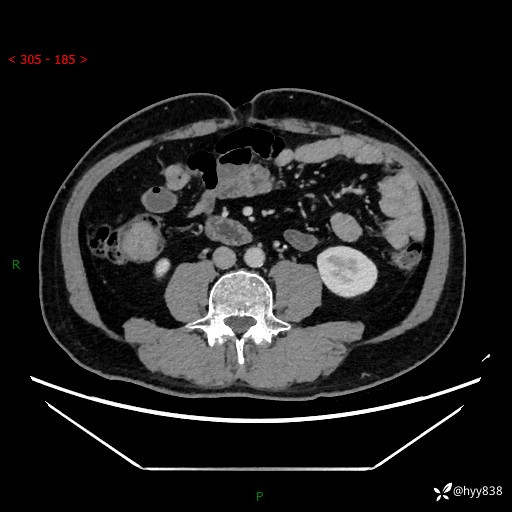

腹部CT增强扫描(外院CT平扫)

两期CT值:75hu 82hu